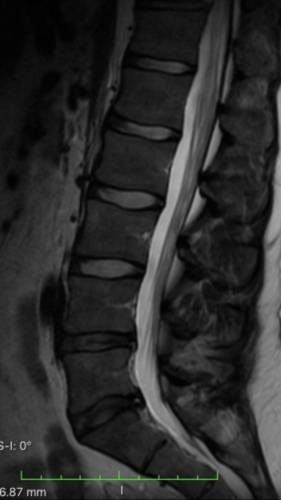

I had spinal surgery on my L4-L5 disc years ago because it was herniated and causing me to be unable to walk. The surgery went well but now I'm having issues on and off with my legs again. They go numb often and sometimes it will last for 5min or so before I can move. I went for an MRI recently to see what was going on and they sent me home w the images. I have a decent idea of what I am looking at but would appreciate some clarity. I'm not quite sure what my spine looked like after surgery so not certain what is considered normal in this case since it's been worked on. Could you please help me read my MRI? Thanks so much!

a couple more images.